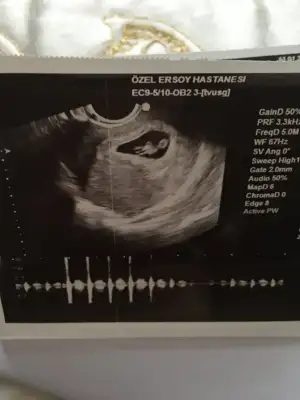

Karından bakıldıysa kız sag kız sol erkek7 haftalık ben erkek olucak gibi hissediyorum tabi cinsiyet öğrenmemize daha var ama bi tahmin isterim![]()

7 haftalık ben erkek olucak gibi hissediyorum tabi cinsiyet öğrenmemize daha var ama bi tahmin isterim![]()

Hayır karında bakılmadı vajinal ultrasonKarından bakıldıysa kız sag kız sol erkek